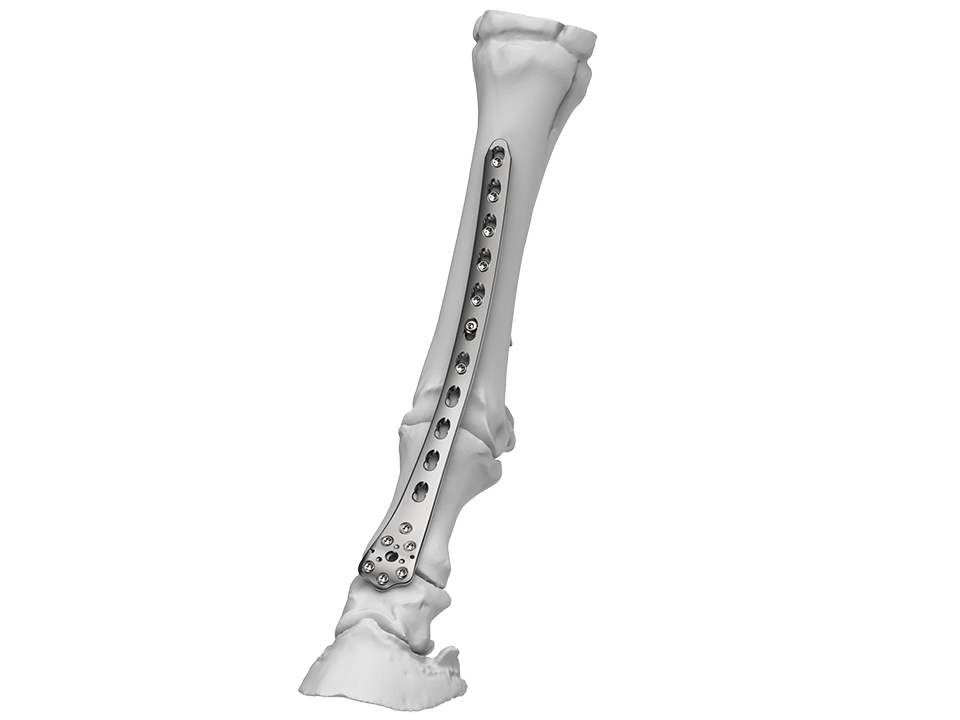

Plate design

The LCP Distal Femur Plate (DFP) is a precontoured, low profile plate that features combi-holes along the shaft accepting 4.5 mm/5.5 mm cortex screws in the dynamic compression unit portion and 5.0 mm locking screws in the threaded portion (Fig 2). The threaded locking holes in the plate head accept 5.0 mm locking screws and 4.5 mm/5.5 mm cortex screws. The LCP DFP, available in a left and a right version, was initially indicated for distal shaft, supracondylar, intraarticular, extraarticular, and periprosthetic fractures in the human femur. Implants and instruments of the LCP DFP are fully compatible with the 4.5/5.0 mm LCP Systems. Recently, the LCP DFP (9- and 11-holes, left and right) has been approved for veterinary applications, specifically for comminuted P1 fractures in horses.

The wide and flattened head of the plate has several locking holes which provides a strong fixation in the proximal aspect of the middle phalanx (P2) and the distal aspect of the P1, distal to the area of major comminution. Furthermore, the curved shape allows abaxial fixation into one of the major fragments in P1 or in the medial or lateral condyle of the distal metacarpus/metatarsus when associated with a concomitant condylar fracture. The low profile of the plate permits placement using less invasive fixation techniques.